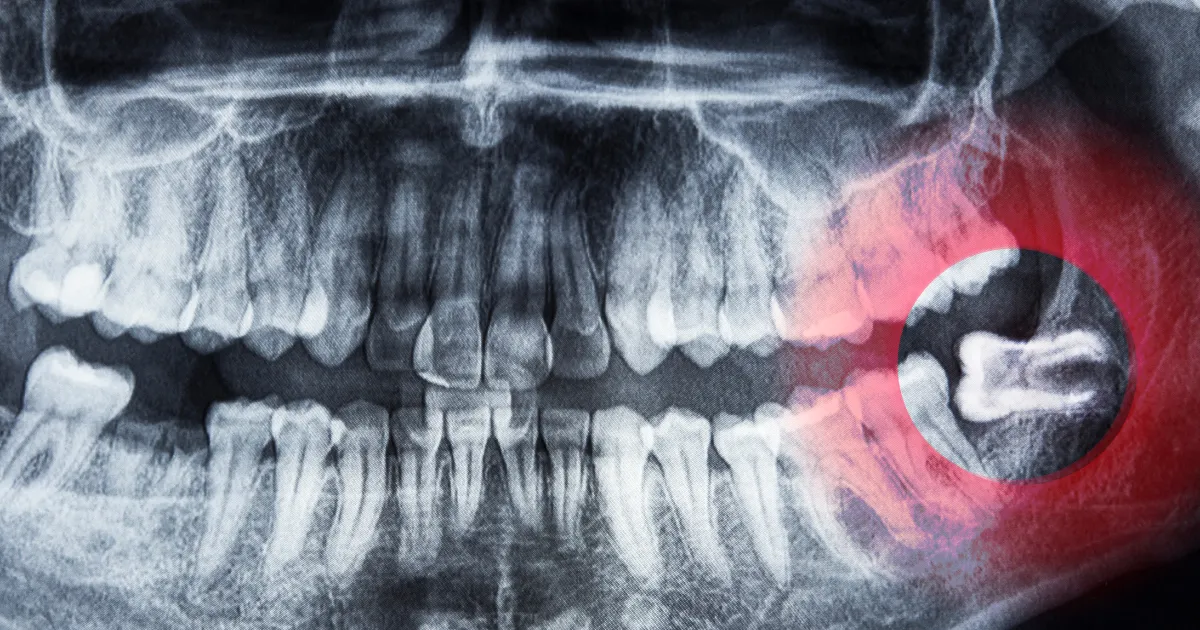

详细的术前诊断

通过X光片和CT扫描,医生可以精准定位智齿的位置以及它与神经的关系,从而评估手术难度,确保手术安全进行。